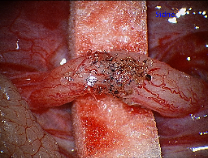

The next step in a vasectomy reversal is to re-approximate the ends of the vas deferens in a tension-free manner. The 10-0 Nylon suture provides a water-tight closure for the sperm to travel through the vas deferens. If larger sized suture is used, it can cause obstruction in the vasal lumen itself.